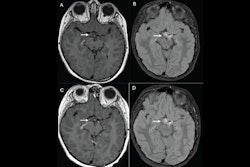

Presenter Dr. Leo Wolansky of UConn Health in Farmington, CT, and colleagues found that using gadopiclenol at 0.05 mmol/kg with central nervous system MRI was just as effective as using gadobutrol at 0.1 mmol/kg. The findings were part of the PICTURE trial, which compared the two agents.

The study showed that gadopiclenol performed on par with gadobutrol in all of the visualization criteria (p < 0.0001). But it actually outperformed gadobutrol when it came to the two measures of the percentage of enhancement and lesion-to-background ratio (p < 0.0001).

What's more, readers preferred gadopiclenol MRI images in 44.8% to 57.3% of the exams. As for adverse events, their incidence was similar between the two agents, with a rate of 14.6% for gadopiclenol and 17.6% for gadobutrol; these events were mainly injection site reactions and weren't serious, Wolansky noted.